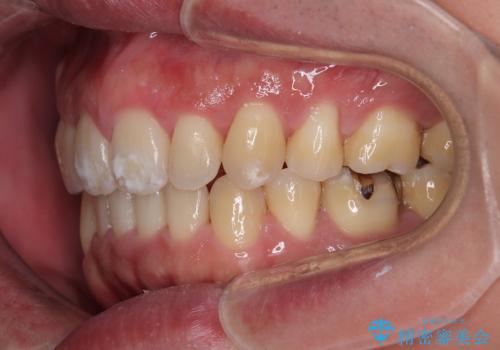

2年から2年半の治療期間を想定しており、予定通りの期間で無事に終了することができました。

唇や顎先に力を入れないなくてもスムーズに唇を閉じることができるようになりました。